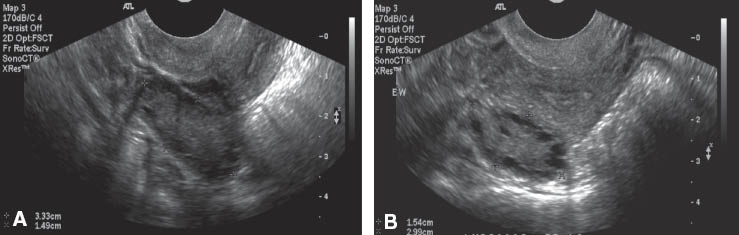

Morphological characteristics of ovaries include number and location of the follicles distributed within the ovary, stromal echogenicity, and vascularization (17). Silfen et al. reported that 100% obese PCOS and 75% non-obese PCOS patients had multiple peripherally oriented ovarian follicles, compared with 31% of controls (11). Shah et al. and Pawelczak et al. reported that more than 80% of obese adolescent PCOS patients had >10 follicles located peripherally (10, 14). Figure 1 shows the peripherally located follicles in obese and non-obese PCOS adolescents, compared with a normal ovary. Figure 2 shows both transabdominal and transvaginal ultrasound of a polycystic ovary in an overweight PCOS adolescent.

(A) Transabdominal longitudinal ultrasound image of the right ovary in an overweight adolescent with PCOS. (B) Transvaginal longitudinal ultrasound image of the right ovary in the same patient. The quality of the image is improved with transvaginal ultrasound.

In adolescents who are not sexually active, pelvic ultrasonography is preferred using the transabdominal approach. The resolution of the image may be suboptimal, especially in overweight and obese individuals, making evaluation of ovarian morphology more difficult (21). The use of 2D sonography to assess ovarian stromal echogenicity has been criticized for user subjectivity and inaccurate reproducibility (8). With the advent of 3D ultrasound, the transverse plane of the pelvis can be visualized, allowing for the ovary to be examined simultaneously in three orthogonal planes and for ovarian stroma measurement. Direct measurement of the ovarian stromal volume is done by subtraction of the total follicular volume from the total ovarian volume (8, 22).

3D ultrasound assessment of ovarian morphology is less subjective than 2D ultrasound and allows for a more precise and objective assessment of ovarian volume, total ovarian area, stromal area, and overall blood flow within the ovary (8). The hyperechogenicity of the ovarian stroma seen in patients with PCOS is useful for differentiation of multicystic ovaries normally seen in adolescence (17). Using a 3D transabdominal probe in the adolescent population to assess the S/A ratio may pose a challenge as the resolution of the scan is decreased because there is an increased distance between the probe and ovary, compared with the transvaginal method. Research studies need to be done to assess whether using a 3D transabdominal probe is a feasible method to assess ovarian features, especially S/A ratio, in both the non-obese and obese adolescent population.